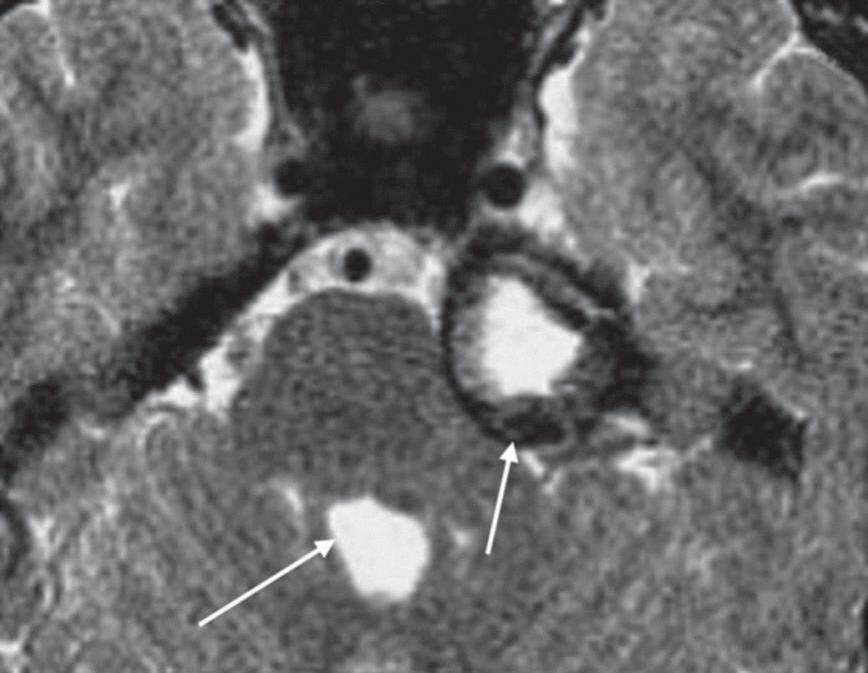

A sequência gradiente-eco balanceado steady state (FIESTA, CISS, TrueFISP) é uma sequência muito rápida, com aquisição volumétrica das imagens, adquiridas com espessura de corte muito fina e sem intervalo entre os cortes. Esta sequência demonstra conteúdo fluido de liquor, perilinfa ou endolinfa com sinal hiperintenso, com acurácia, estruturas neurais e a relação com estruturas vasculares na fossa posterior (Figs. 1-12 e 1-13).

1-12. Sequência volumétrica. Sequência axial volumétrica: liquor com sinal hiperintenso (seta curta), sétimo e oitavo nervos cranianos na cisterna do ângulo pontocerebelar (seta longa).